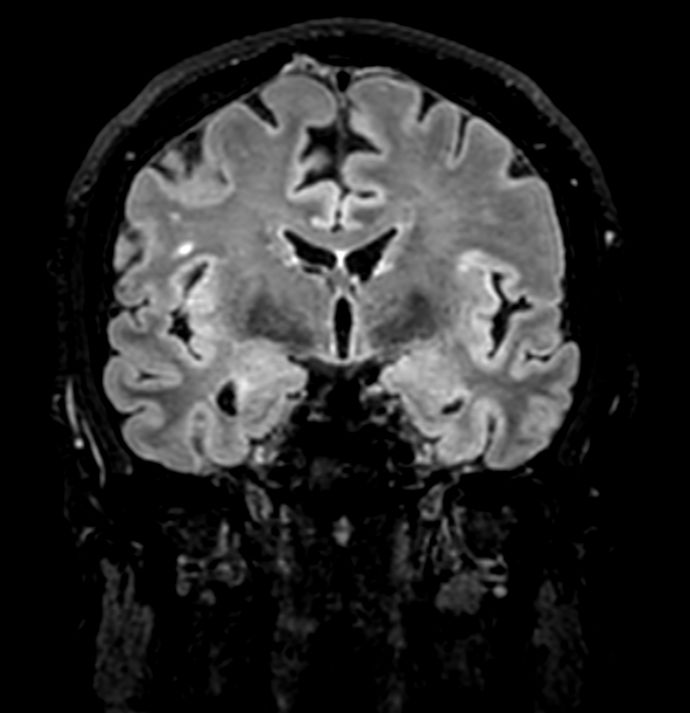

3D VIEW - T2w FLAIR (coronal reformat)

3D VIEW - T2w TSE (coronal reformat)